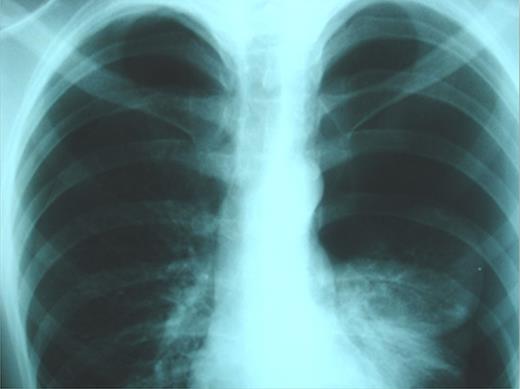

On emergency basis, the patient was managed with bilateral tube thoracostomy through the fifth intercostal spaces. During hospitalization, both lungs were gradually expanded; the use of continuous aspiration was necessary for a couple of days, in order to achieve complete expansion of the left lung (Fig. 2). Both chest tubes were removed on the fifth day of hospitalization. Next day the plain X-ray revealed recurrence of pneumothorax on the left side (Fig. 3). A chest tube was reinserted. Continuous suction was used and complete expansion of the left lung was succeeded. The tube was removed after 5 days; no recurrence took place at this time. During the next 3 days the patient remained under observation; serial physical examinations and chest X-rays were normal and the patient was discharged home.

Complete bilateral lung expansion after insertion of chest tubes.